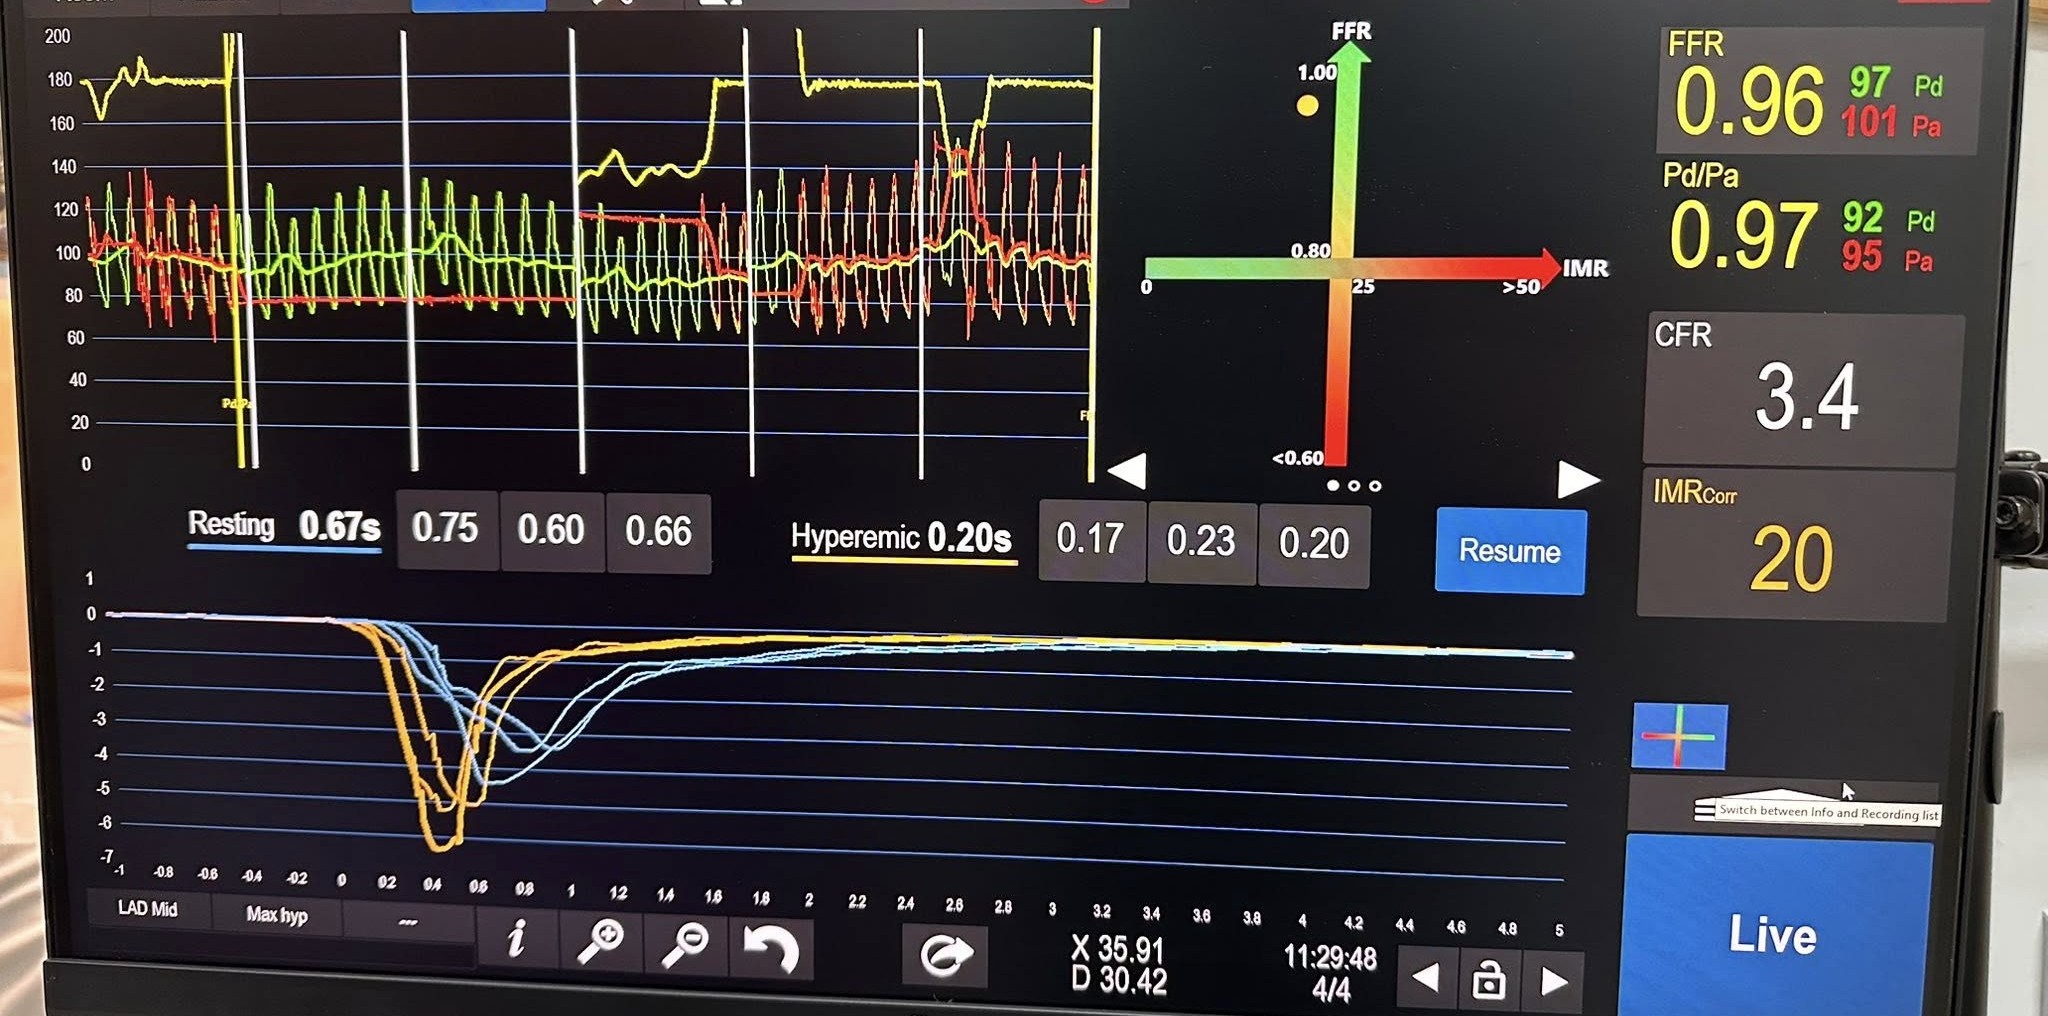

“Danas smo obavili dva slučaja kompletne invazivne koronarne fiziologije i kod jednog pacijenta potvrdili dijagnozu vazospastične angine. Ponosan sam na tim i zahvalan svom mentoru, dr Ivanu Iliću, kao i kompaniji “Abbott Medical“ na podršci’“, izjavio je dr Aleksandar Janjičić, načelnik Odjeljenja za internističke grane JZU Bolnica “Sveti Vračevi“ Bijeljina.

On je naglasio da je ovo značajan napredak za pacijente iz cijele regije, jer se sada dijagnostičke procedure koje su do sada bile dostupne samo u referentnim centrima van zemlje, mogu obaviti i u Bijeljini.

„Izvođenjem današnjih procedura JZU Bolnica „Sveti Vračevi“ u Bijeljini je postala dio registra centara jugoistočne Evrope za ispitivanje fiziologije krvnih sudova srca“, naglasio je dr Janjičić.